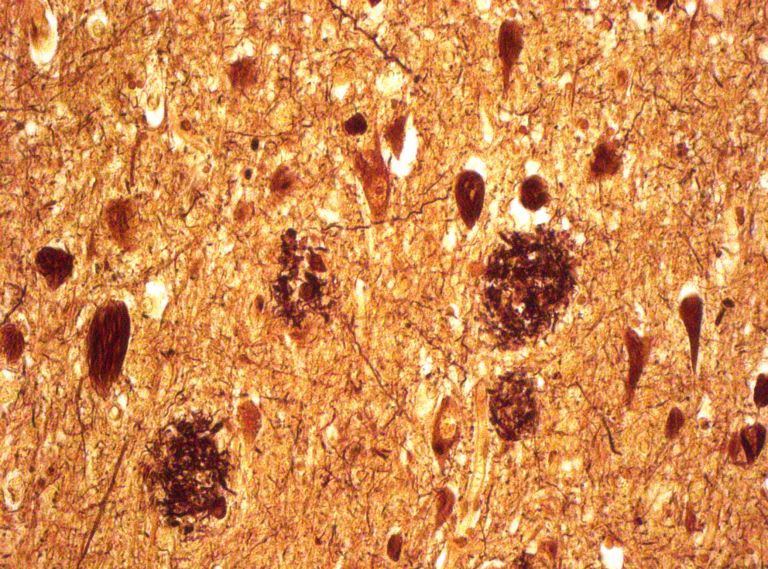

Der deutsche Neuropathologe Max Bielschowsky entwickelte eine Färbemethode, die mittels Versilberung speziell die senilen Plaques bei Alzheimer-Patienten sichtbar macht. Post mortem, natürlich. Ein schönes Bild mit makabrem Hintergrund. Mehr über die biochemischen Veränderungen im Gehirn erfahren Sie in den Artikeln Altern – (nicht nur) eine Frage der Biologie und Das Gehirn in seinen reifen Jahren.

Bild von Dr. Jakob Matschke, Leiter AG forensische Neuropathologie, Universitätsklinikum Hamburg-Eppendorf